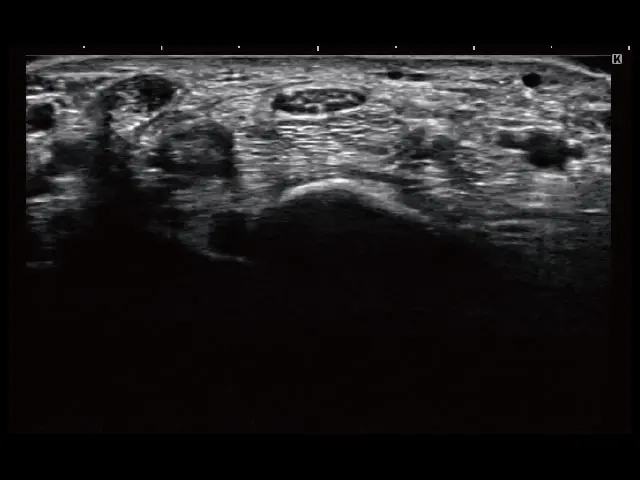

イメージギャラリー

イメージ画像を表示する